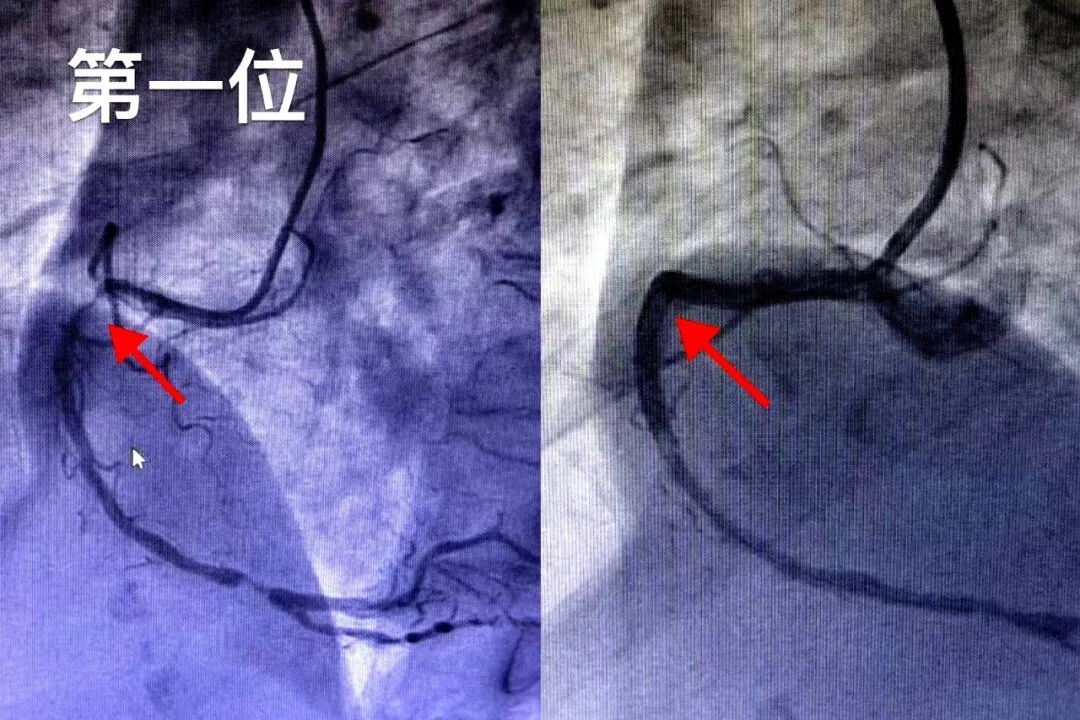

第二位患者为48岁男性,因胸痛6小时紧急就诊,属于典型的急性ST段抬高型心肌梗死。造影提示其心脏最重要的供血血管——左前降支(LAD)近段急性完全闭塞,情况万分危急。团队立即行紧急再灌注治疗,以最快速度开通闭塞血管,最大程度挽救了心肌、降低了坏死面积,为患者赢得了宝贵的预后改善机会。